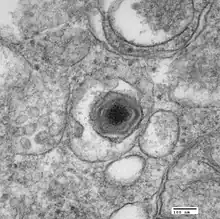

Electron micrograph of a virus particle

ASFV is a large (175–215 nm),[6] icosahedral, double-stranded DNA virus with a linear genome of 189 kilobases containing more than 180 genes.[7] The number of genes differs slightly among different isolates of the virus.[8] ASFV has similarities to the other large DNA viruses, e.g., poxvirus, iridovirus, and mimivirus. In common with other viral hemorrhagic fevers, the main target cells for replication are those of monocyte, macrophage lineage. Entry of the virus into the host cell is receptor-mediated, but the precise mechanism of endocytosis is presently unclear.[9]

The virus encodes enzymes required for replication and transcription of its genome, including elements of a base excision repair system, structural proteins, and many proteins that are not essential for replication in cells, but instead have roles in virus survival and transmission in its hosts. Virus replication takes place in perinuclear factory areas. It is a highly orchestrated process with at least four stages of transcription—immediate-early, early, intermediate, and late. The majority of replication and assembly occurs in discrete, perinuclear regions of the cell called virus factories, and finally progeny virions are transported to the plasma membrane along microtubules where they bud out or are propelled away along actin projections to infect new cells. As the virus progresses through its lifecycle, most if not all of the host cell's organelles are modified, adapted, or in some cases destroyed.

Macrophage cell in early stages of infection with ASFV

Assembly of the icosahedral capsid occurs on modified membranes from the endoplasmic reticulum. Products from proteolytically processed polyproteins form the core shell between the internal membrane and the nucleoprotein core. An additional outer membrane is gained as particles bud from the plasma membrane. The virus encodes proteins that inhibit signalling pathways in infected macrophages and thus modulate transcriptional activation of immune response genes. In addition, the virus encodes proteins which inhibit apoptosis of infected cells to facilitate production of progeny virions. Viral membrane proteins with similarity to cellular adhesion proteins modulate interaction of virus-infected cells and extracellular virions with host components.[1]